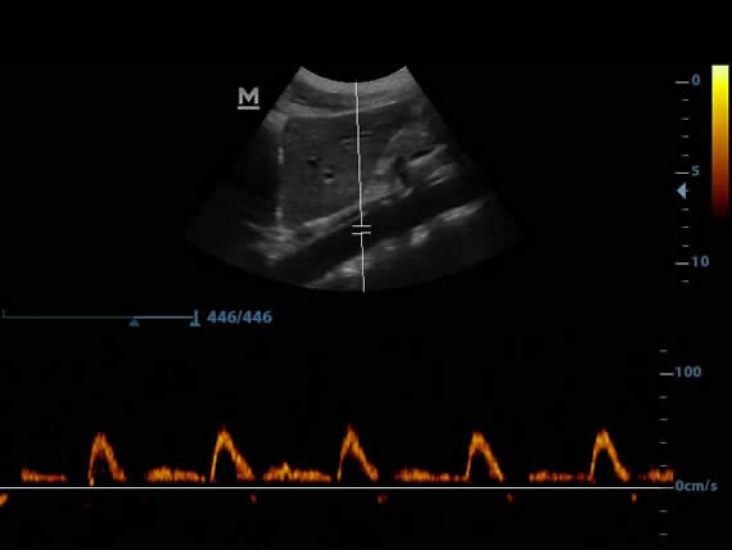

PW

PW Doppler dan Pelacakan Otomatis menampilkan detail aliran darah untuk diagnosis yang bersifat lebih komprehensif.